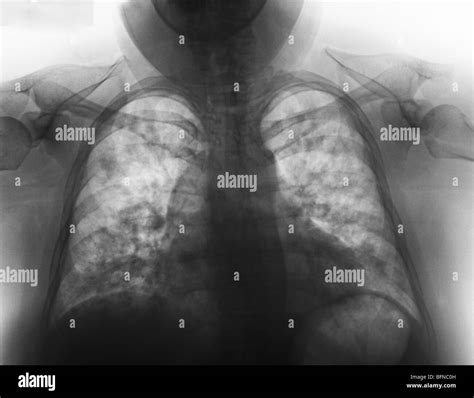

Consolidation

Consolidation refers to the replacement of air in the lungs with fluid, cells, or other material. It appears as an area of increased opacity on the X-ray. Common causes include pneumonia and pulmonary edema.

• Pneumonia: Inflammation of the lungs, often caused by bacterial, viral, or fungal infections.